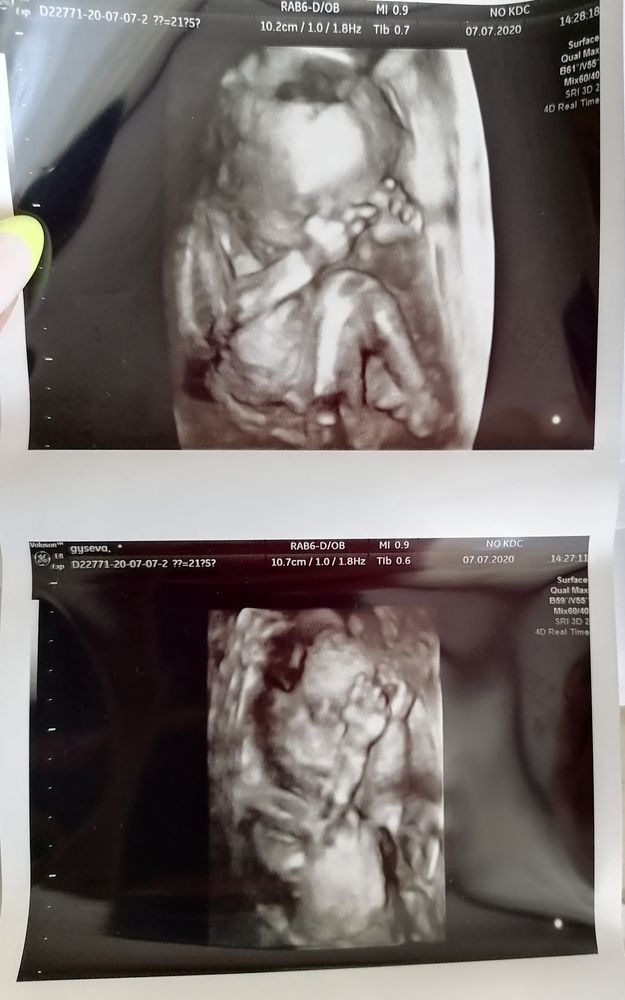

Делина Белая, да не за что) да, это будет правильное решение! Мне точно сказали на 3д УЗИ и показали даже + фоточки сделали Изображение Это примерно в 24 недели было, если не ошибаюсь

16.09.2021

Марина, Ааааа, как сидит 😍 Личико спрятала) Вот как раз через неделю у меня по месячным будет 24 недели и 6 дней, вот тогда и схожу. Уже должны рассмотреть)